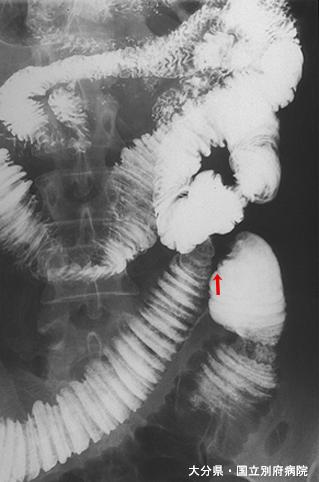

上肠系膜静脉血拴症所致小肠坏死的手术病例

炎症性・溃疡性疾患/缺血性大肠炎

小肠/2个以上

检查方法

X线

40以上